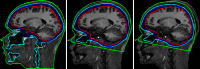

Subject-specific four-layer boundary element method (BEM) electrical forward head models for four participants, generated from magnetic resonance (MR) head images using NFT ( www.sccn.ucsd.edu/wiki/NFT ), were used to simulate electroencephalographic (EEG) scalp potentials at 256 recorded electrode positions produced by single current dipoles of a 3-D grid in brain space. Locations of these dipoles were then estimated using gradient descent within five template head models fit to the electrode positions. These were: a spherical model, three-layer and four-layer BEM head models based on the Montreal Neurological Institute (MNI) template head image, and these BEM models warped to the recorded electrode positions. Smallest localization errors (4.1-6.2 mm, medians) were obtained using the electrode-position warped four-layer BEM models, with largest localization errors (~20 mm) for most basal brain locations. When we increased the brain-to-skull conductivity ratio assumed in the template model scalp projections from the simulated value (25:1) to a higher value (80:1) used in earlier studies, the estimated dipole locations moved outwards (12.4 mm, median). We also investigated the effects of errors in co-registering the electrode positions, of reducing electrode counts, and of adding a fifth, isotropic white matter layer to one individual head model. Results show that when individual subject MR head images are not available to construct subject-specific head models, accurate EEG source localization should employ a four- or five-layer BEM template head model incorporating an accurate skull conductivity estimate and warped to 64 or more accurately 3-D measured and co-registered electrode positions.